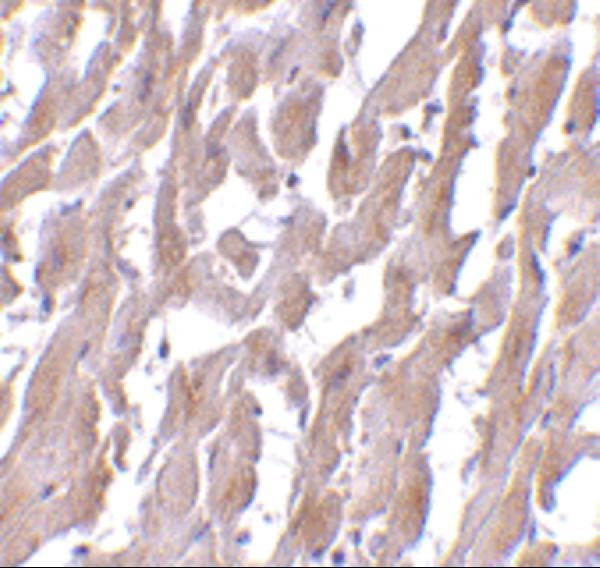

Cytoplasm. Nucleus.